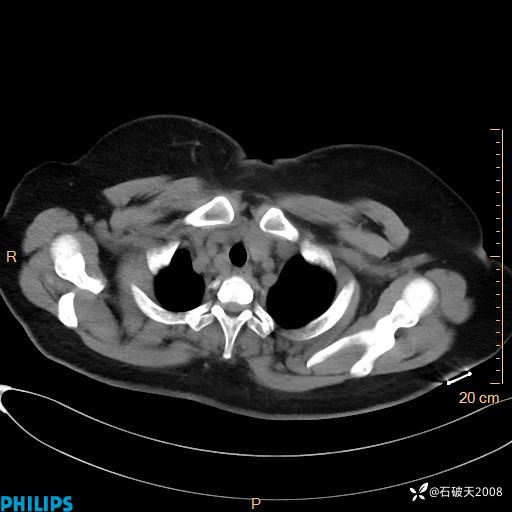

肺结节病?纵膈型肺癌?淋巴瘤?有点意思,欢迎围观

女 52岁 主 诉:咳嗽10余天,咳痰2天。

现病史:10余天前无明显诱因出现咳嗽,呈阵发性干咳,伴咽喉部发痒,无咽痛,无咳痰,无鼻塞、流涕、打喷嚏,无发热、畏寒、寒颤,无头痛、头晕,无胸闷、胸痛,无反酸、烧心,无腹痛、腹泻,无尿频、尿急,无皮疹等,在当地诊所求治,给予口服药物治疗(具体不详),病情无好转。遂在当地社区卫生服务中心开具口服药物治疗(具体不详),疗效欠佳。2天前出现咳痰,在我院门诊求治,行胸部CT提示肺部感染,建议住院,患者要求口服药物治疗,目前仍咳嗽、咳白色粘痰,白天量多,夜间自觉喉部喘鸣音,遂再次来院就诊,以“肺部感染”为诊断收入院。发病以来,神志清,精神可,饮食可,夜间睡眠差,大小便正常,近期体重无明显变化。

纵隔窗